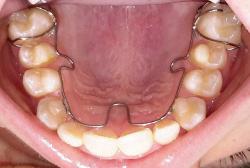

Brown is highly trained in ALF (Advanced Light Force) therapy. He has over 500 hours in ALF therapy training and has lectured around the world teaching ALF techniques with Dr. Nordstrom, the creator of the ALF appliances. The ALF appliances are thin, conservative appliances that can be used on the upper and lower arches. They hide behind the teeth, are removable and are basically invisible when being worn. This innovative treatment approach is used to address neurological, orthodontic and orthopedic issues, and the benefits are vast. Each appliance is unique to the patient and designed by the doctor to achieve specific goals relating to health, beauty and function. No ALF appliance is the same, and treatment is pain-free.

ALF Therapy has proven to be an extremely valuable tool for those patients who have:

• A need for facial guidance

• Palate expansion

• Narrow palates

• Breathing issues

• TMJ dysfunction

• Craniofacial pain

• Crowded/crooked teeth

• An avoidance for extractions

• Crossbite, overbite or underbite

• Cranial asymmetry

• Sleeping problems — snoring

• Recommendations for jaw surgery

Our ALF appliances are certified by Dr. Darick Nordstrom. He has personally instructed our ALF-certified technicians on the proper design and fabrication techniques to ensure that each technician is capable of creating authentic ALF appliances worthy of certification. The seal below is his stamp of approval.